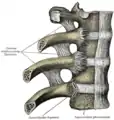

Un disque intervertébral (DIV) ou fibrocartilage intervertébral est un cartilage qualifié de fibreux, qui se trouve entre presque toutes les vertèbres de la colonne vertébrale (sauf entre C1/C2). Chaque disque est formé d'un fibro-cartilage mixte (se rapprochant d'une symphyse), et permet un faible mouvement des vertèbres. Il agit aussi comme un ligament maintenant les vertèbres ensemble. Son rôle d'amortisseur des chocs est crucial et son altération physiologique explique les nombreuses pathologies du dos.

Les disques intervertébraux constituent environ 1/5 de la hauteur totale du rachis. Passé 75 ans, la hauteur des disques intervertébraux est divisée par deux, réduisant ainsi fortement les mouvements du rachis.

Le rapport corpéro-discal (hauteur du disque intervertébral hauteur du corps de la vertèbre) varie selon le segment du rachis. Plus ce rapport est élevé, plus le segment du rachis sera mobile.

Le disque intervertébral a pour fonction de séparer les vertèbres les unes des autres et de permettre le mouvement de ces dernières grâce à ses propriétés d’articulations.

Schéma vertèbre et disque intervertébrale

Schéma vertèbre et disque intervertébrale Image d'une cage d'arthrodèse par voie d'abord antérieure, il existe également des prothèses (ou disque artificiel) permettant de conserver la mobilité